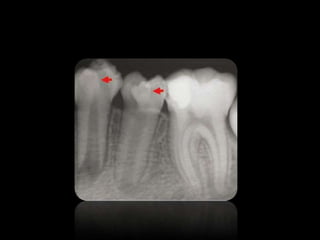

6.

CARIES